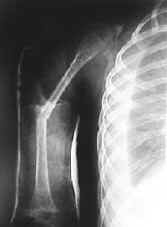

En junta multidisciplinaria y reevaluándose las placas histológicas se logra establecer que es una enfermedad de Gorham. Entre los tratamientos instaurados se utilizan alendronatro 5 mg/día. En 1999 el paciente presenta derrame pleural y una fractura patológica del húmero, que fue manejada de manera expectante (Figura 2).

Figura 2. Presencia de fractura patológica en húmero derecho, con férula de yeso.